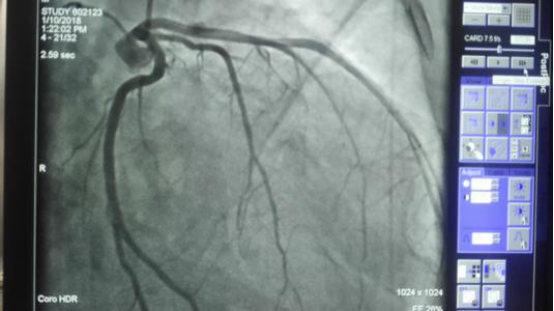

达芬奇是人类历史上一位传奇人物 , 世人对他的第一印象往往是一个技术高超的画家 , 然后才是音乐家、数学家和医学家 。 达芬奇生前创作了许多手稿 , 通过这些手稿后人了解到达芬奇是一个奇才 , 在500多年前他就已经对人类的心脏进行精细的绘画 。 从他的手稿中甚至还能够看到一些细微的结构 , 比如心肌小梁 。

他将亚里士多德的思想融入到自己的研究中 , 最终提出“心脏帮助呼吸并为人体供热”的观点 。 中世纪时期人体解剖学在欧洲兴起 , 医学家们有机会对心脏进行更为准确的认知 。 达芬奇也诞生于中世纪的欧洲 , 他在对心脏进行解剖和研究后 , 在纸上绘画出了心脏内部结构 , 其中就包括了一种十分复杂的肌肉纤维“心肌小梁” 。

在过去 , 即使医学家们知道心肌小梁的存在 , 却始终无法准确地认知它的存在 。 起初医学家们认为心肌小梁的作用只是让流过的血液升温 , 没有其他重要的作用 , 现在看来这种认知并不准确 。 随着生物技术的不断发展 , 现代生物技术已经能够较为全面地认知人体情况 , 曾有研究指出心肌小梁在心脏发育早期就出现了 。

根据研究发现 , 心脏是人体最早长出来的器官 , 受精完成后大约一个月的时间 , 心脏就开始跳动 。 众所周知 , 心脏的跳动需要氧气的供给 , 因此科学家们认为早期就已经出现的心肌小梁主要就是给心脏提供氧气 , 但在心脏发育完成后它就不再发挥供氧作用了 , 因此医学家认为心肌小梁在成人的心脏中并不发挥重要作用 。

这次研究让医学家们有机会认清楚心肌小梁在心脏中的真实作用 。 先是英国的科学家从英国生物样本库中获取了50万份人类样本 , 然后对其中的心脏结构进行深入研究 , 并且分析了不同地区的基因差异 。 然后是来自欧洲分子生物学实验室的研究人员收集了2.5万张心脏磁共振图像 , 然后利用人工智能算法对这些图像进行分析 。

最后的研究结果刊登在了《自然》期刊上 , 在论文中研究人员指出心肌小梁的真实作用一直都被低估了 , 实际上它在成人的心脏中同样发挥重要作用 。 研究人员通过研究发现 , 如果心脏中存在心肌小梁 , 那么心室内表面就会变得不光滑 , 如果不存在心肌小梁 , 心室内表面就会变得光滑 。 比起光滑的表面 , 不光滑的表面能够减少血液输出时的阻力 。